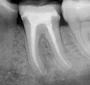

Root Canal Treatment

There are various reasons for root canal treatment namely:

• Decay in the tooth involving the pulp, nerve and blood vessel

• Irreversible pulpitis due to trauma or an old leaking restoration

• Acute pulpitis

• Fracture into the pulp

• Re-preparation of an old root canal treatment

The aim of root canal therapy is to remove all the toxins and debris that has formed by bacteria from the canal. The inside of the tooth is cleaned and disinfected so that it is prepared for a root canal filling. The highly qualified and professional dentist carefully files the canals with profile rotating instruments and during this process, we constantly wash the canals and disinfect them.

Root Canal Treatment Dentists South Africa

Location of the canals are sometimes a challenge. We work with Dental Loupes that gives magnification and digital xrays and apex locators to ensure the best accuracy, 3D xrays are sometimes also indicated to assess the situation. As an added disinfection we use laser energy to kill of the bacteria, this also gives excellent pain relief. After a session of filing and cleaning the canal, and the patient is symptom free, the canal is then filled with a rubber-like material called Gutta-Percha.

To protect the tooth, we then restore it with a crown or filling. After restoration, the tooth continues to function like any other tooth. This procedure is done with local anaesthetic and can be completely pain free. In some severe septic cases, the anaesthetic may not be very effective and the patient may have discomfort or pain initially but this occurs infrequently. In some cases where the tooth is severely infected a course of antibiotics might be needed.